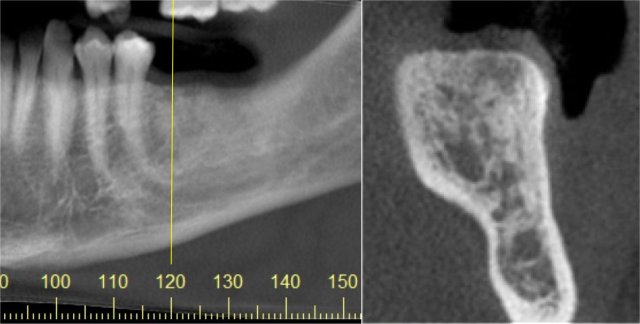

CBCT Implant Imaging

Show bone volume, nerve canal in the lower jaw, sinus floor on upper jaw. Other relevant anatomy can be identified to see if adequate bone is available for implant placement.